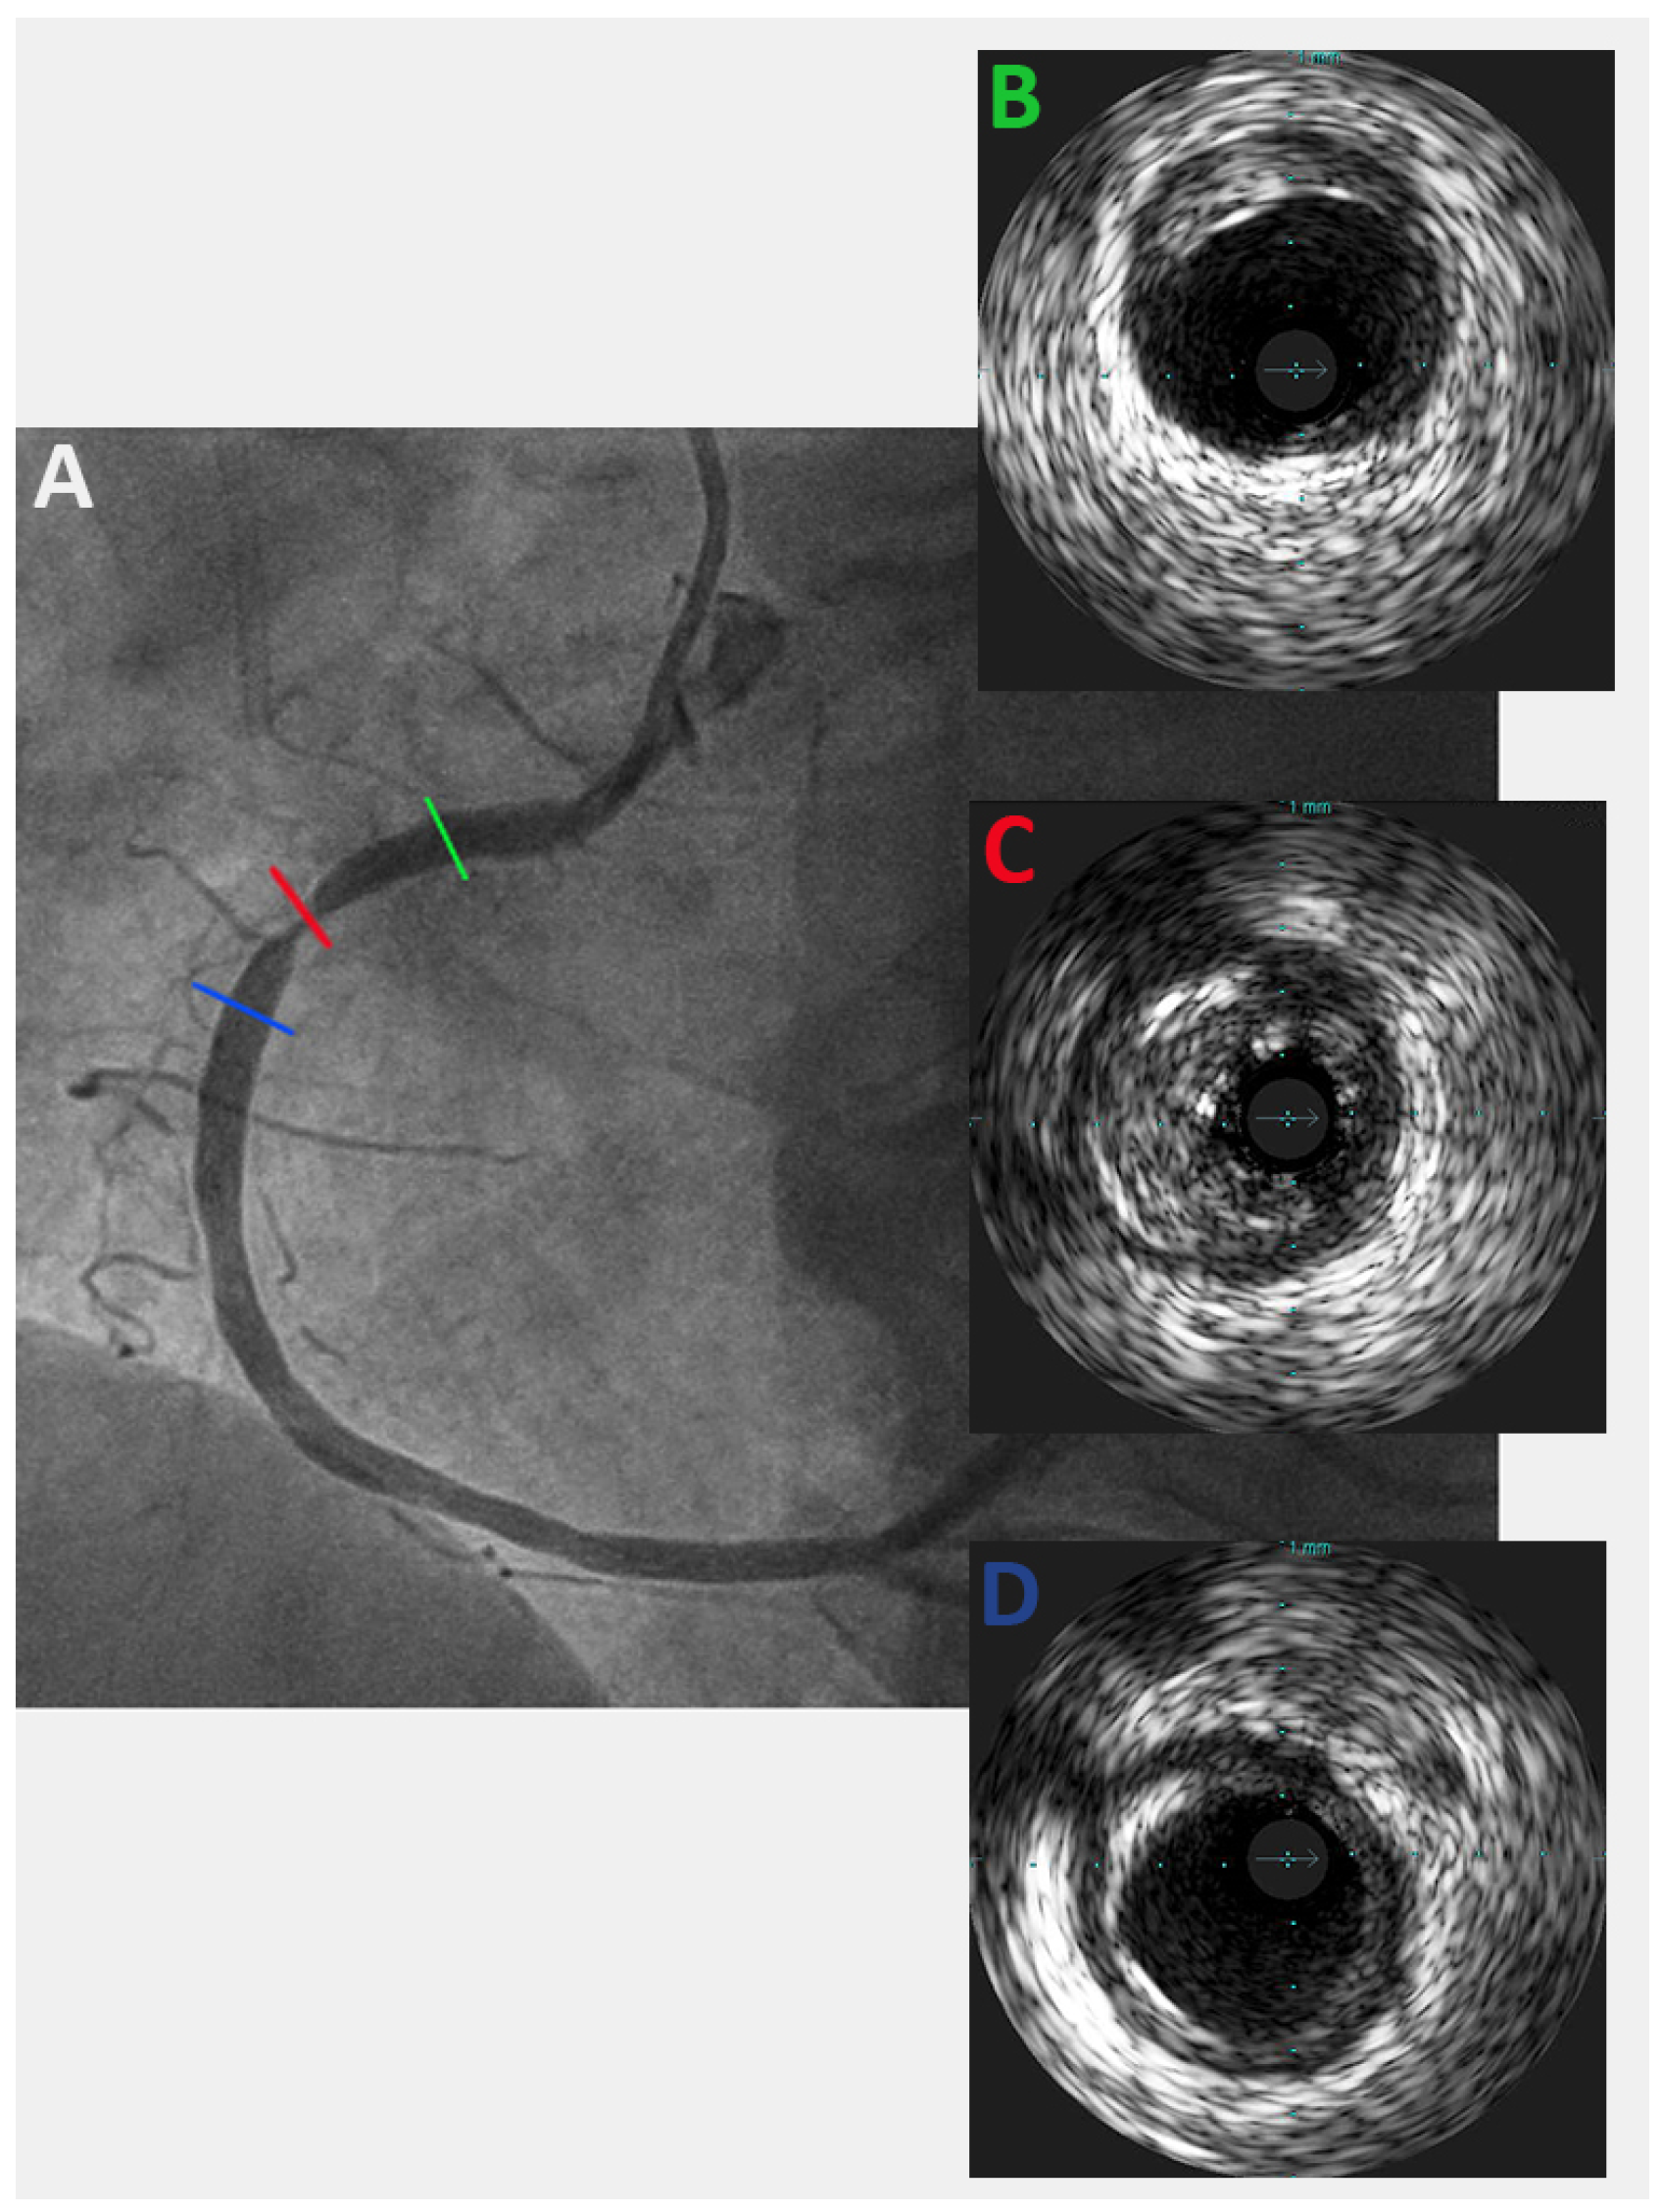

Impressive Late Stent Recoil of a Drug-Eluting Resorbable Magnesium Coronary Stent

Case description